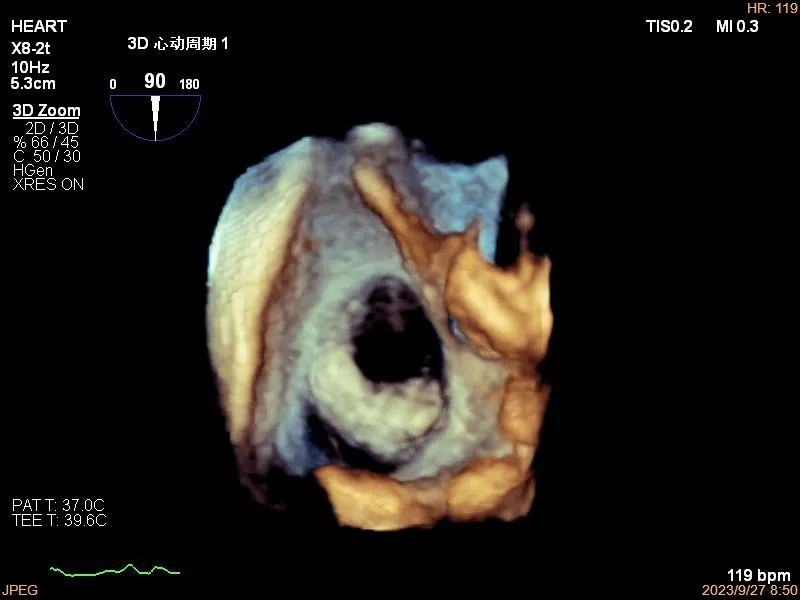

3、房间隔缺损(ASD)的诊断及分型:3D TEE可精确显示缺损大小、形状及边缘,可动态显示其形态变化。

房间隔缺损三维图